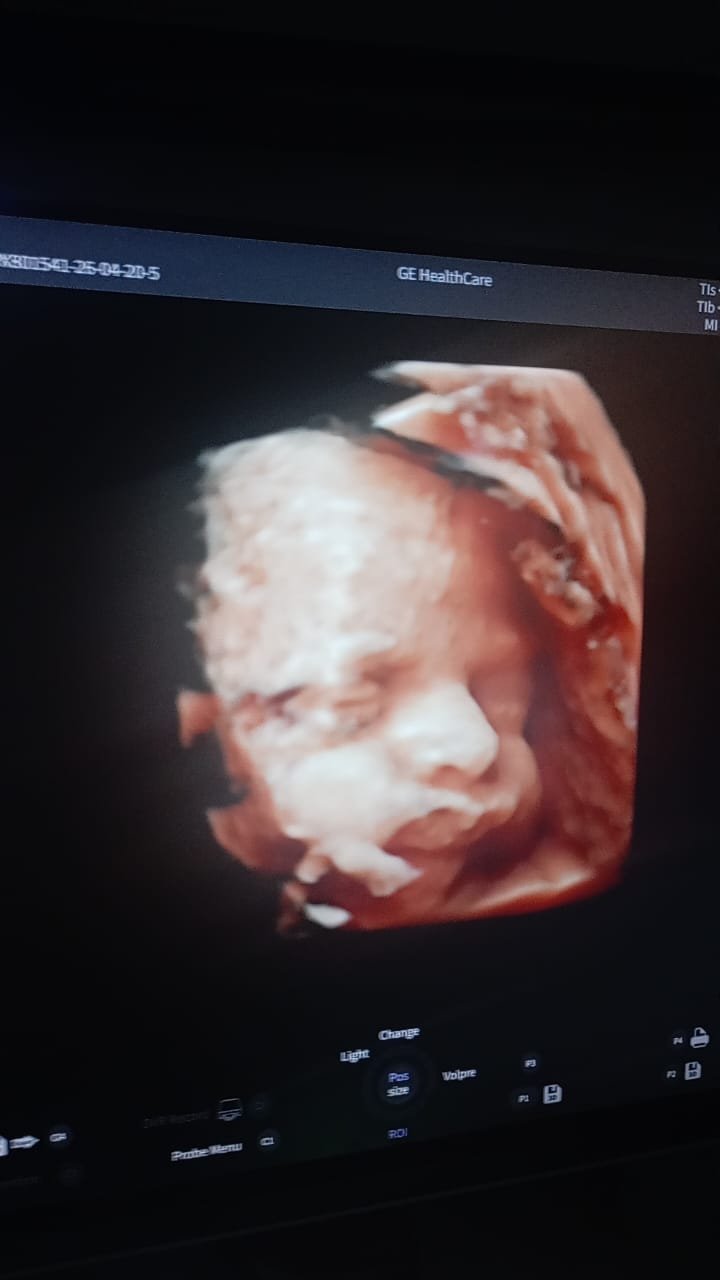

وأكد الدكتور أحمد البيلي وكيل وزارة الصحة، أن هذه الدورة تأتي في إطار خطة وزارة الصحة والسكان ومديرية الشئون الصحية لتطوير خدمات الأشعة، خاصة مع توريد أول جهاز سونار رباعي الأبعاد بمستشفى الزقازيق العام، والذي سيتم تشغيله فور الإنتهاء من الدورة التدريبية، بما يساهم في تحسين دقة التشخيص ورفع كفاءة الخدمات الطبية المقدمة للمرضى بمستشفى الزقازيق العام، مشيراً إلى أهمية التدريب العملي على أحدث الأجهزة والتقنيات الطبية.

وأشار الأستاذ محمود عبدالفتاح مدير الإعلام والعلاقات العامة بالمديرية، إلى أن التدريب تضمن محاضرات وورش عمل عن تقنيات السونار ثلاثي ورباعي الأبعاد، وآليات تحسين جودة الصورة ودقة التشخيص، وفحص حالات فعلية داخل قسم الأشعة، لرفع كفاءة أداء الأطباء في مجال تشخيص أمراض الأجنة، كما تم تدريب أطباء الأشعة وأطباء النساء والتوليد على الاستخدام الأمثل للتقنيات الحديثة، كما قدم وكيل الوزارة شهادات اجتياز الدورة التدريبية للمتدربين، لافتاً أن الفعاليات شملت تكريم رئيس وفريق مكافحة العدوى بمستشفى الزقازيق العام لحصولهم على المركز الأول على مستوى المحافظة بناء على تقييم الوزارة الفترة السابقة.